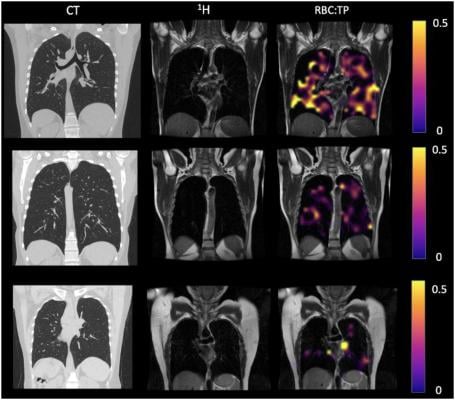

Example CT, proton, proton and RBC:TP imaging from post-Covid-19 condition participants. The top row is a participant with RBC:TP = 0.49, the middle row is a participant with RBC:TP of 0.31, and the bottom row is a participant with RBC:TP = 0.24. Imaging showed little to no discernible damage on CT, and yet highly heterogeneous and low RBC:TP in the lungs of non-hospitalized post-Covid-19 condition participants. RBC:TP = Hyperpolarized 129Xenon MRI lung ratio of red blood cell spectral peak to tissue phase spectral peak. Image courtesy of the Radiological Society of North America

“In a collaboration between the University of Oxford and the University of Sheffield, we have been able to identify abnormalities in the lungs of both hospitalized and non-hospitalized participants using a novel imaging technique, Hyperpolarized Xenon 129MRI, or Hp-XeMRI,” said the study’s senior author, Fergus Gleeson, M.B.B.S., from the Department of Oncology, University of Oxford and Department of Radiology, Oxford University Hospitals NHS Trust. “These abnormalities are not apparent on conventional imaging, and in some individuals were detected up to a year after their initial COVID-19 infection.”

Hp-XeMRI has shown promise in detecting abnormalities of alveolar gas exchange—where oxygen moves from the lungs to the bloodstream and carbon dioxide passes from the blood to the lungs—even when CT scans and lung function tests were normal. Hp-XeMRI enables the assessment of ventilation and gas exchange into red blood cells. It provides regional information of pulmonary vasculature integrity and may be able to identify lung abnormalities not apparent on CT.

“We saw that the ability of gas to transfer from the lungs into the blood stream was less in non-hospitalized patients in comparison to those hospitalized with COVID,” Dr. Gleeson said. “Furthermore, both groups of participants had lower dissolved phase Hp-XeMRI values than healthy participants, pointing to potential defects in either the lining of the lung or the surrounding blood vessels.”

The results showed that there were significant differences in mean red blood cell to tissue plasma ratio between healthy controls and PHC/NHLC participants, indicating potential differences in lung function.

Although participants had normal or near normal CT scores, total lung diffusion capacity for carbon monoxide percentage was significantly lower between NHLC and PHC participants, potentially indicating a decrease in lung function but not structure.